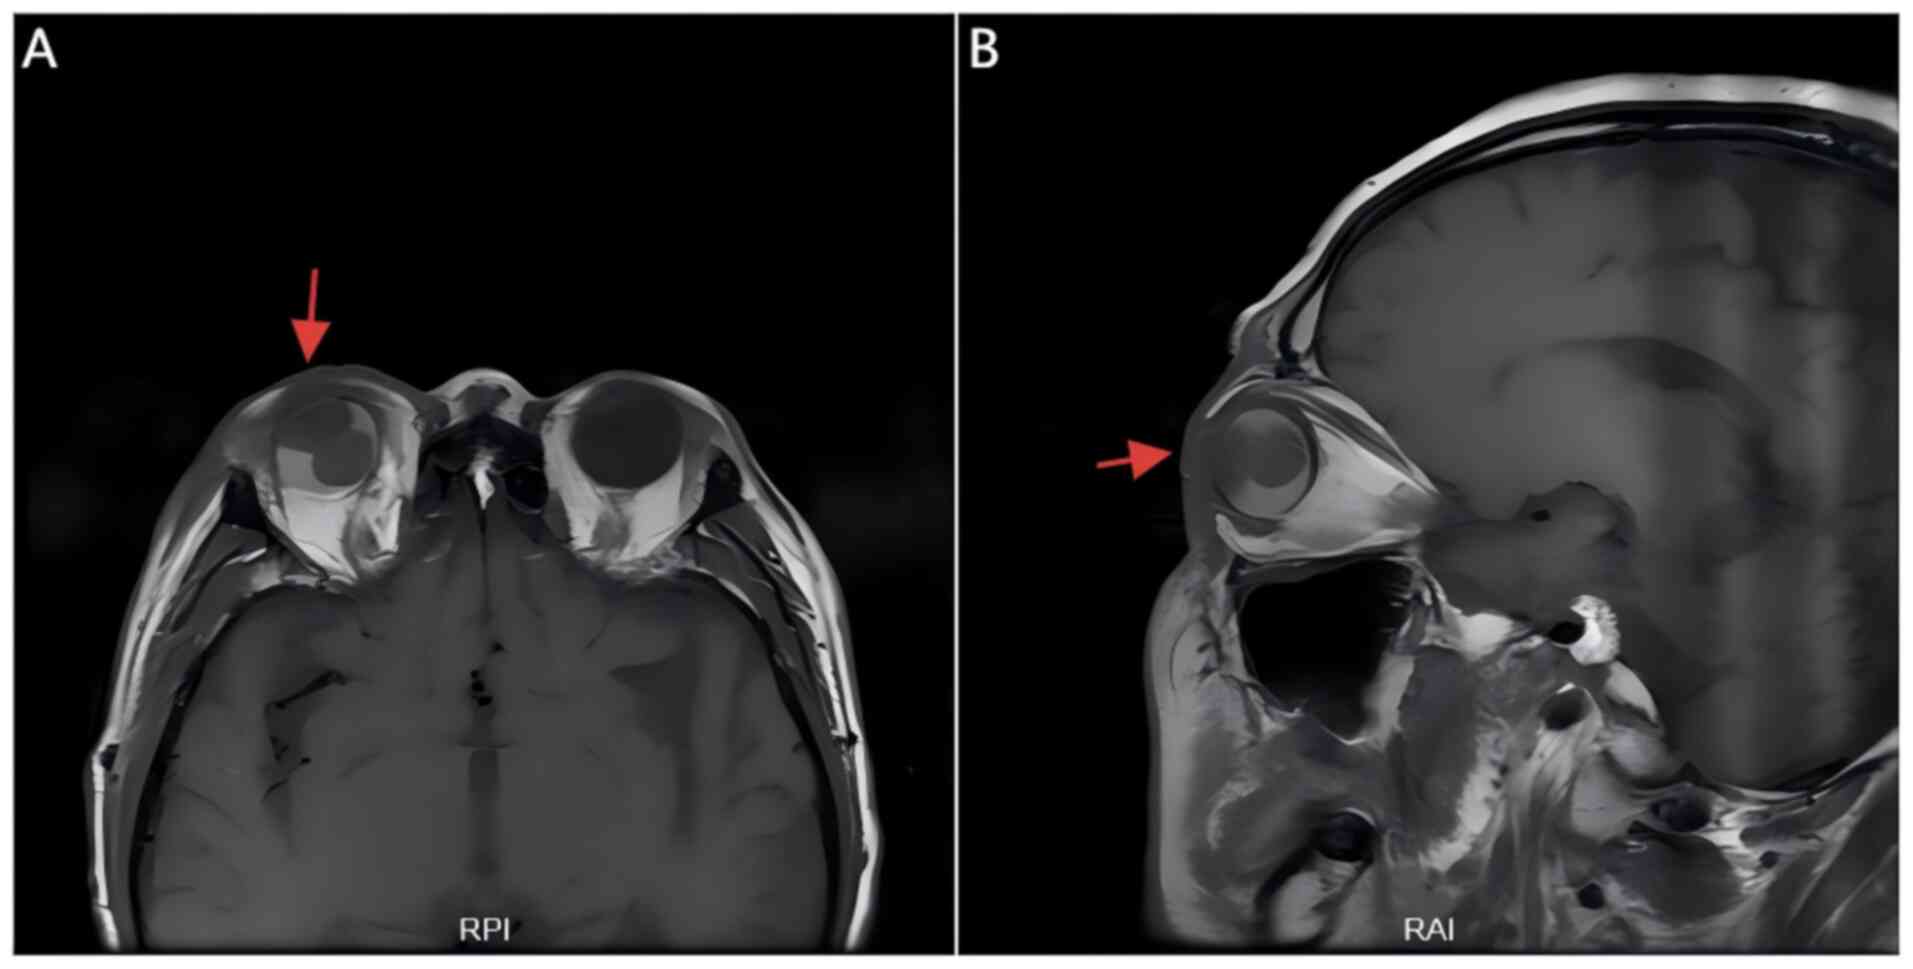

Figure 5

Orbital MRI showing choroidal

metastasis in the right eye. (A) Axial view reveals an intraocular

mass with associated retinal detachment (red arrow). (B) Sagittal

view confirms choroidal thickening and elevation of the retina (red

arrow). RAI, right-anterior-inferior; RPI,

right-posterior-inferior.